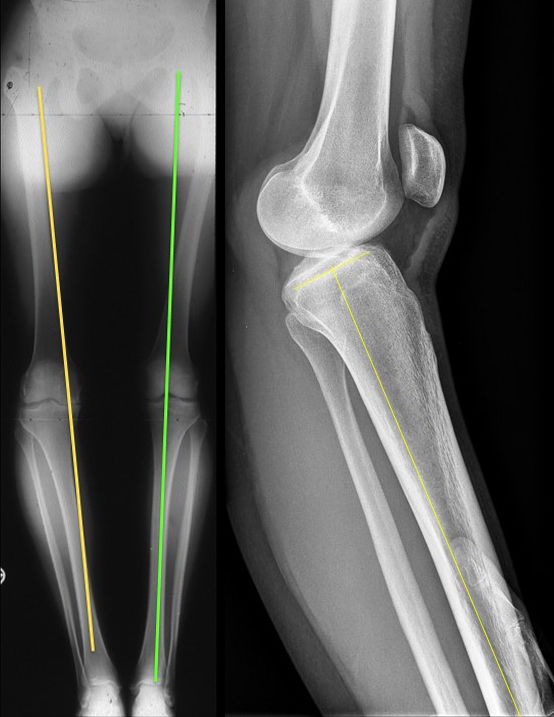

The clinical articles in this issue address several domains of knee and hip surgery. Ligament reconstruction is represented by a practical guide on avoiding tunnel convergence during multiple-ligament knee surgery and a technical review of PCL reconstruction using the INLAY technique. Patellofemoral pathology is examined through technical advice for patellofemoral arthroplasty, while revision hip surgery is addressed through a discussion of the philosophy of total hip replacement revision at Mayo Clinic.